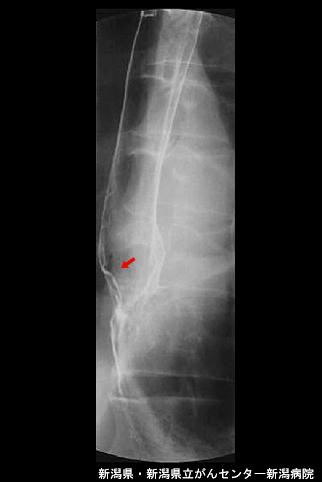

clasificación del pacienteTumor Epitelial Maligno/Adenocarcinoma

parte(separada por órganos)estómago(región)/cardias

método de exámenRayos X

clasificación ectoscópica de tumoresTipo 0(tipo superficial)/Tipo IIa(IIa)

diámetro mayor del tumor10 - 14

grado de penetraciónsm